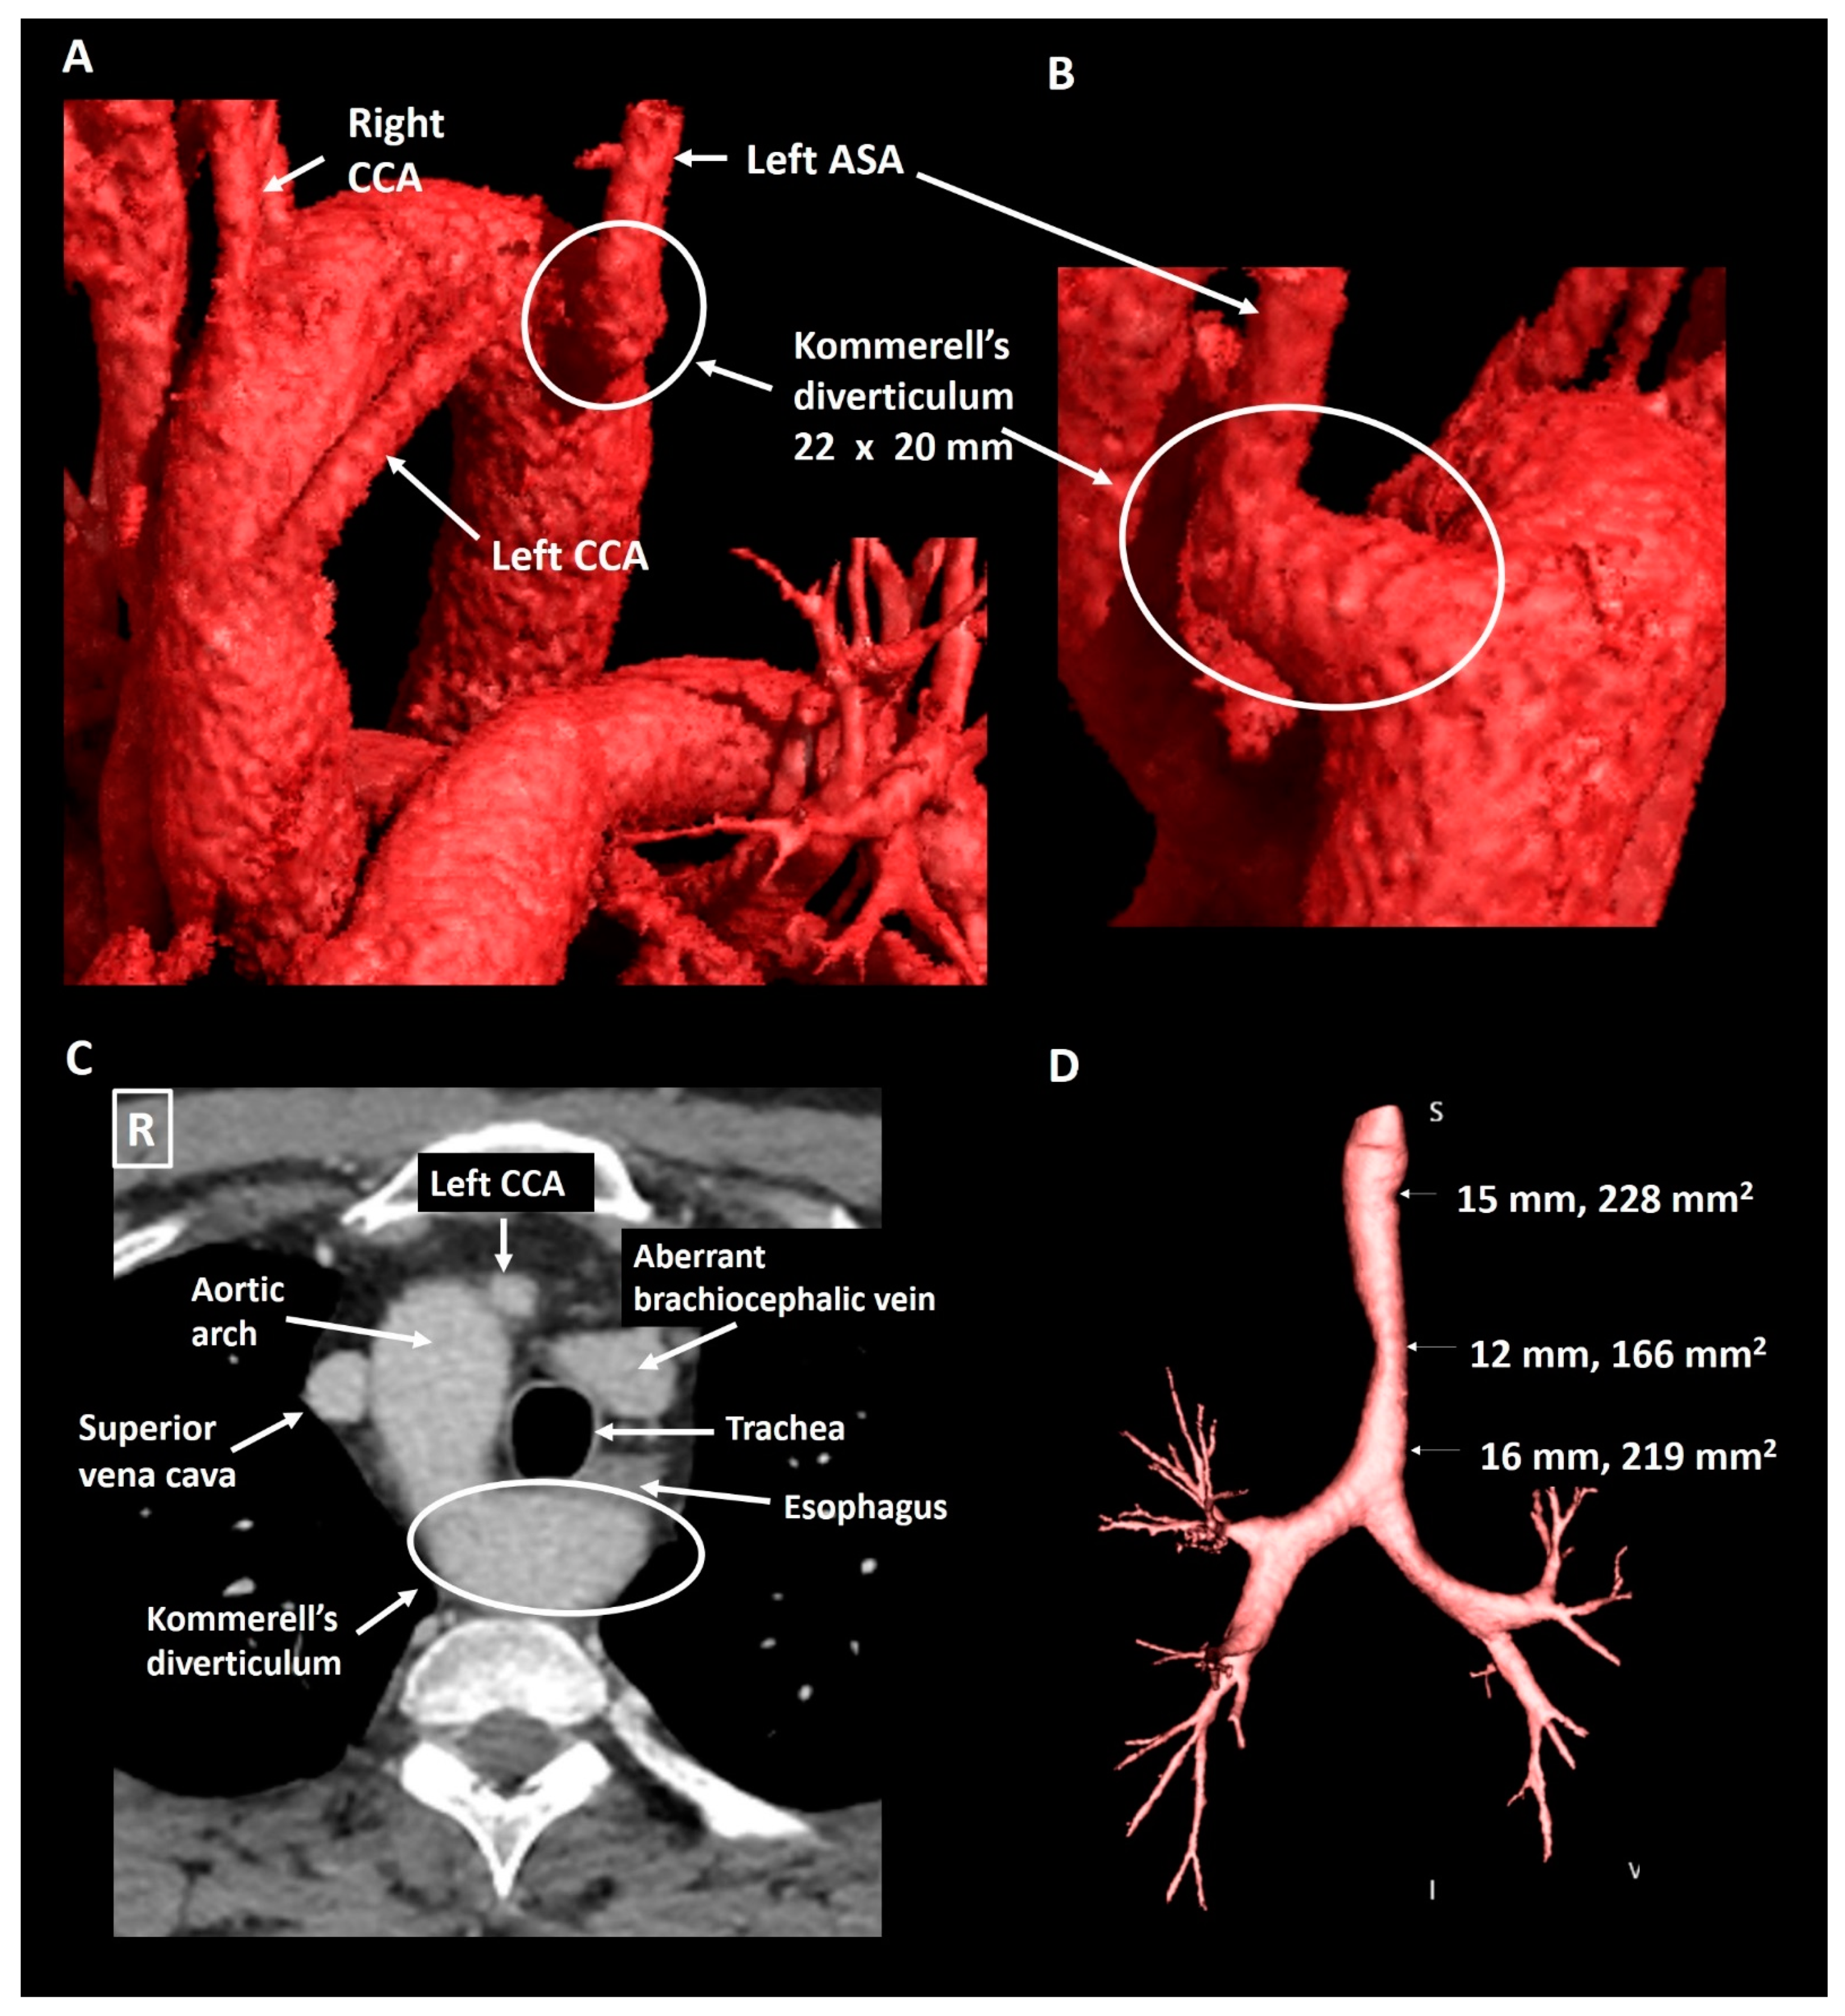

2.1. Patient 1

| Patient 1 | 40 | Male | Right-sided arch, aberrant LSA and KD | Mild tracheal compression | 22 × 20 mm, 319 mm2 | Incidental finding | Structural imaging follow-up |